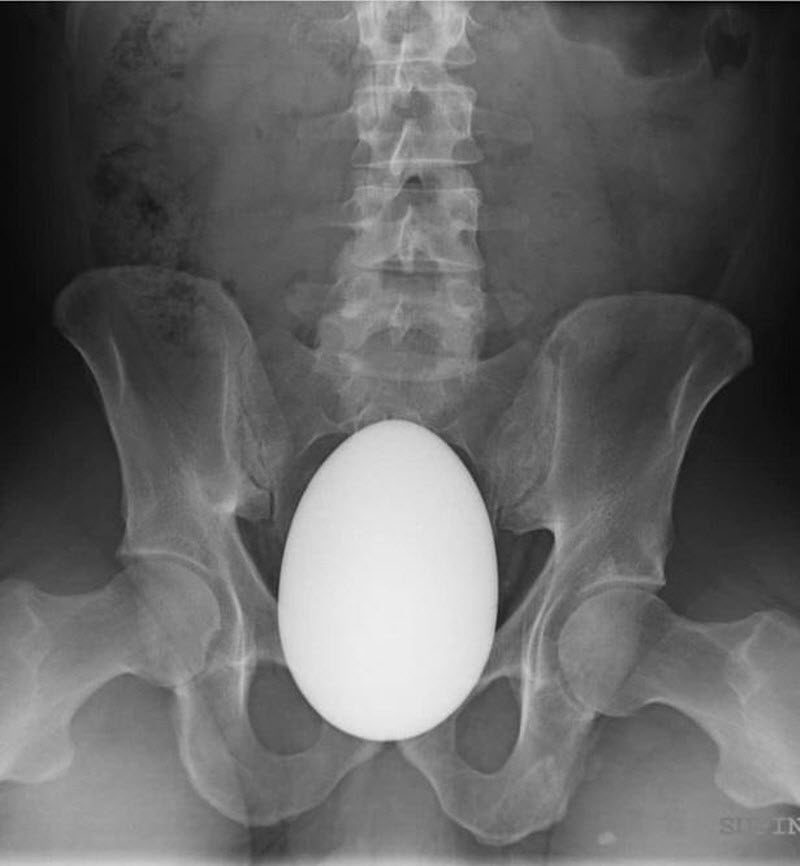

На снимке КТ обнаружили следующее:

В результате срочного хирургического вмешательства на свет появилось перламутровое яйцо. Как оно попало в прямую кишку женщина так и не пояснила